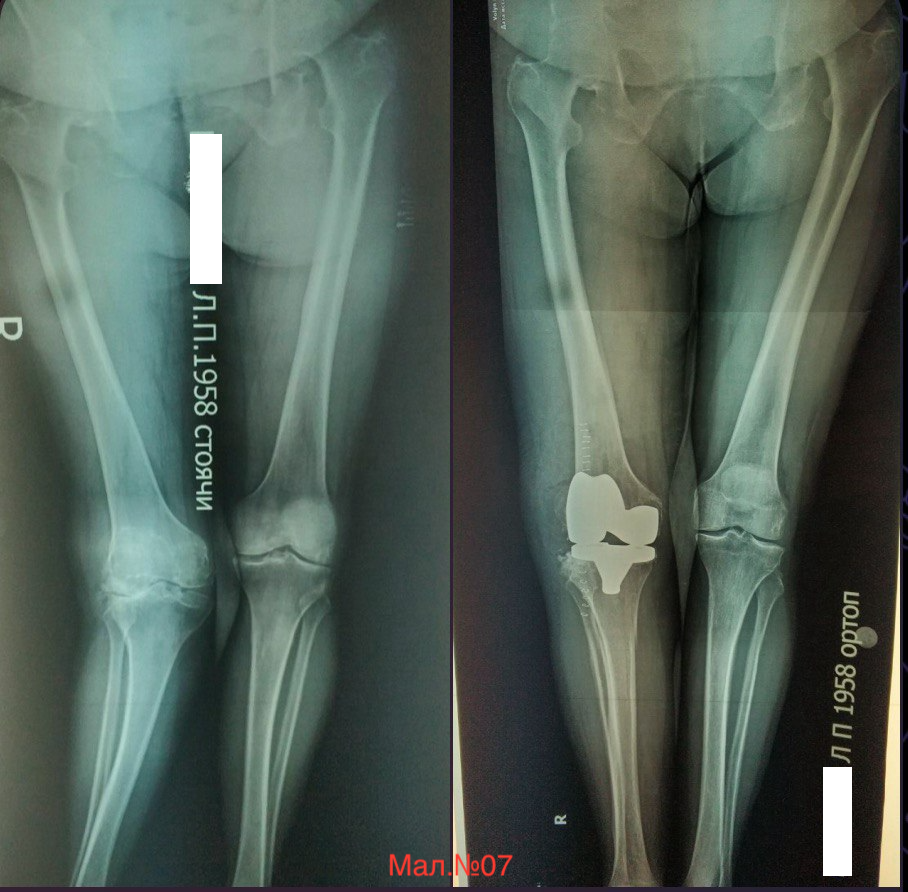

photo_2023-12-13 17.19.59